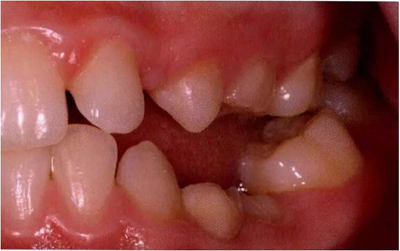

圖3:重度下沉的臨床像

臨床檢查看到合平面出現(xiàn)擾動可做為診斷依據(jù)。下沉乳磨牙位于合平面的凸起端(圖4)。這些牙齒在使用金屬器具敲擊時,會發(fā)出典型的高調(diào),固連“有裂紋茶杯”聲。同時還需要做影像學檢查,以確認繼承恒磨牙是否缺失。